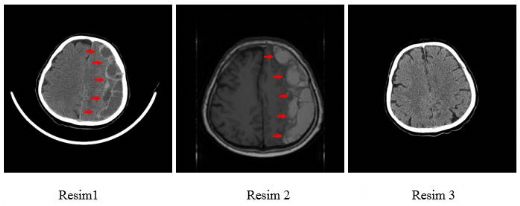

Çocuklarda beyin kanaması, çeşitli nedenlerle meydana gelebilen ciddi bir sağlık sorunudur. Bu durum, çocukların beyin dokusunun zarar görmesine ve yaşamı tehdit eden komplikasyonların ortaya çıkmasına yol açabilir. Beyin kanaması, kafatası içindeki kan damarlarının yırtılması veya sızdırması sonucu meydana gelir ve belirtileri, kanamanın türüne, yerine ve şiddetine bağlı olarak değişiklik gösterir. Beyin Kanaması Türleri Beyin kanamaları, çeşitli tiplere ayrılmaktadır. Bu türler arasında en yaygın olanları şunlardır:

Her bir kanama türü, farklı nedenlere, belirtilere ve tedavi yöntemlerine sahiptir. Belirtiler Çocuklarda beyin kanaması belirtileri, durumun ciddiyetine göre değişiklik gösterebilir. Aşağıdaki belirti ve semptomlar, beyin kanaması yaşayan bir çocukta gözlemlenebilir: